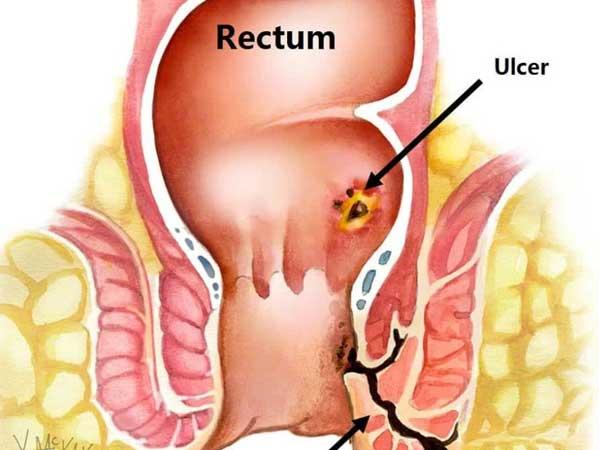

In Ayurveda, anorectal disorders are classified un...